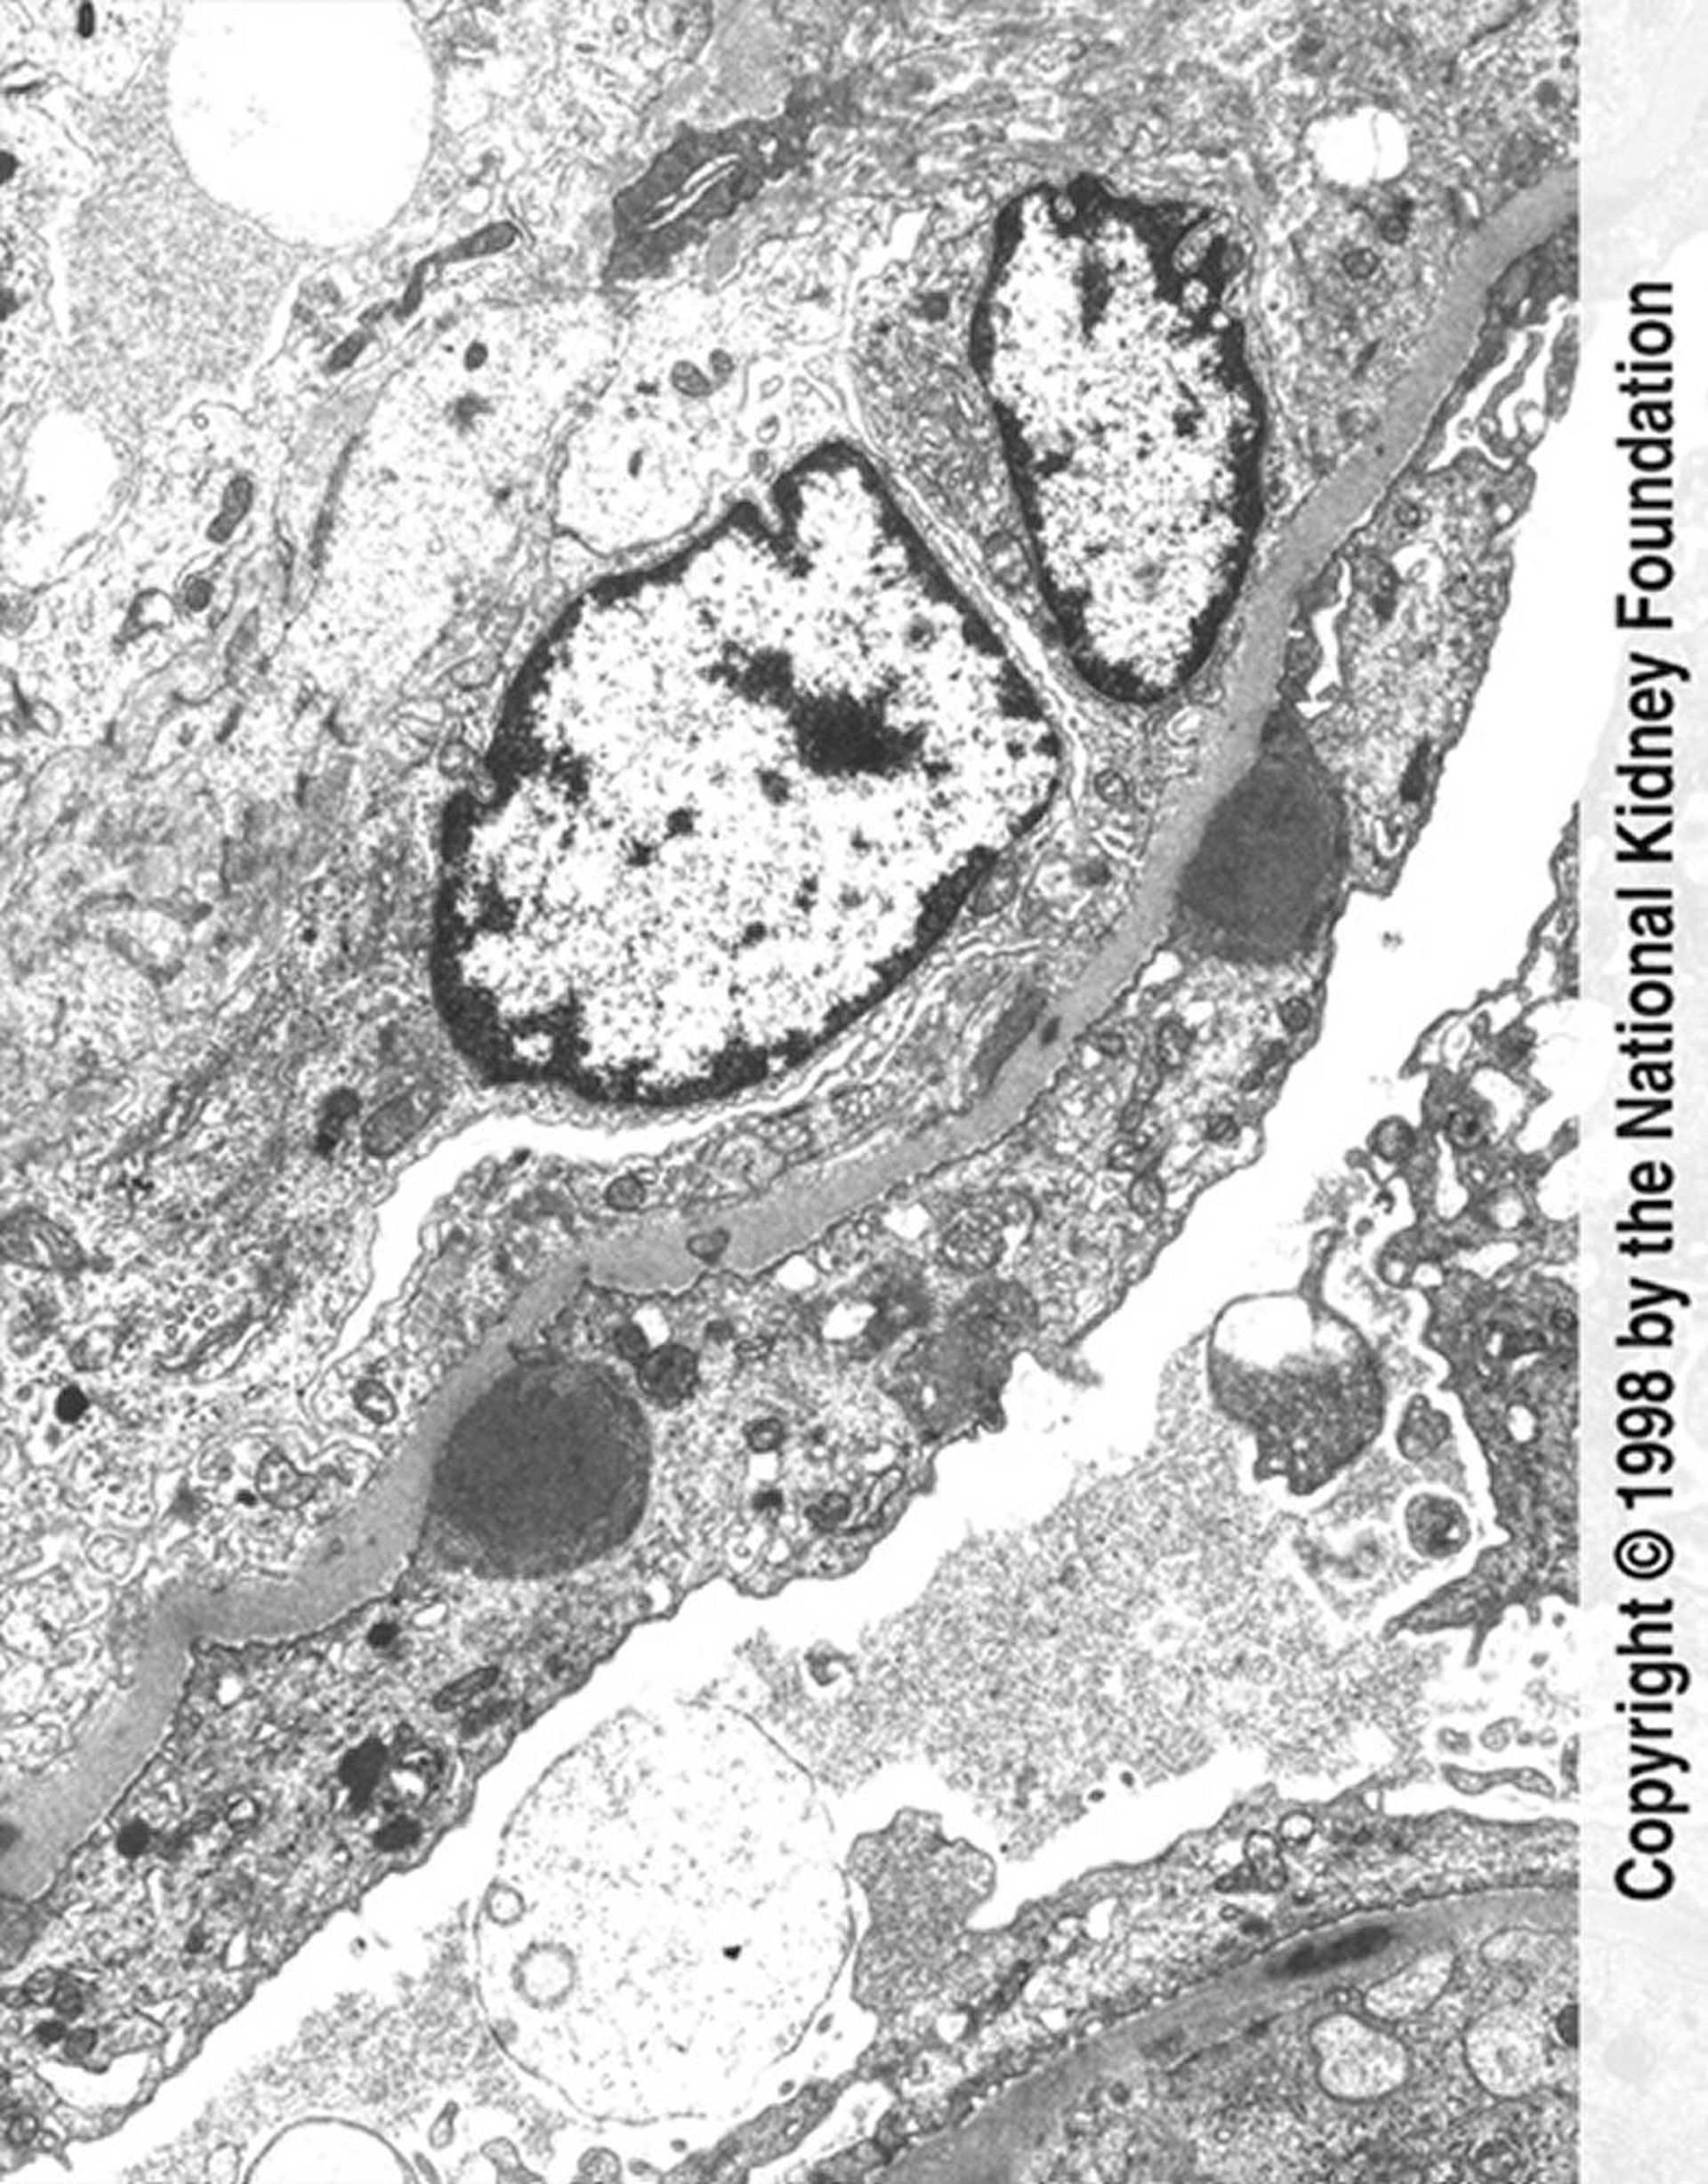

Glomerulonefrite pós-infecciosa (depósitos de complexos imunes)

Depósitos de imunocomplexos na forma de protuberância (cinza escuro) com extenso processo de apagamento e proliferação endocapilar do pé são vistos na micrografia eletrônica (× 11.250).

Image provided by Agnes Fogo, MD, and the American Journal of Kidney Diseases' Atlas of Renal Pathology (see www.ajkd.org).